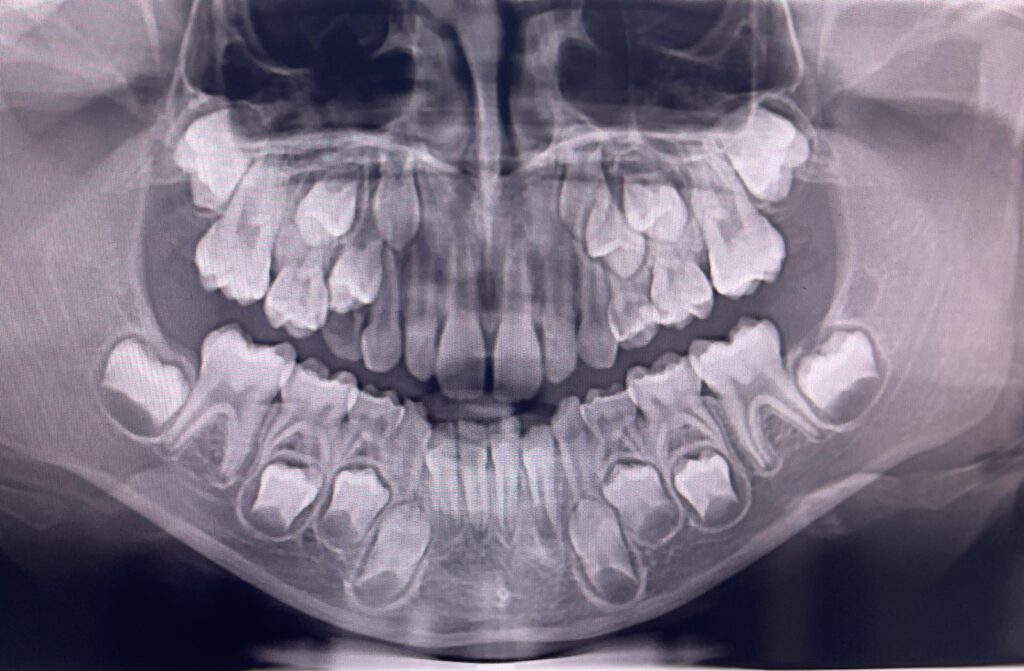

Zdjęcie pantomograficzne

Zdjęcie pantomograficzne – określane również mianem panoramy – umożliwia kompleksową ocenę całej jamy ustnej w jednym ujęciu. Uwidacznia zarówno górny, jak i dolny łuk zębowy, struktury kości szczęk, zatoki szczękowe oraz stawy skroniowo-żuchwowe. Jest niezastąpione w planowaniu leczenia ortodontycznego, implantologicznego czy chirurgicznego, ponieważ dostarcza pełnego obrazu układu stomatognatycznego. W przychodni Poddent zdjęcia pantomograficzne wykonujemy przy użyciu cyfrowych aparatów nowej generacji, co zapewnia wyraźny obraz przy niskiej dawce promieniowania i maksymalnym komforcie pacjenta. To badanie pozwala naszym specjalistom podejmować trafne decyzje diagnostyczne i terapeutyczne, zwiększając skuteczność leczenia.